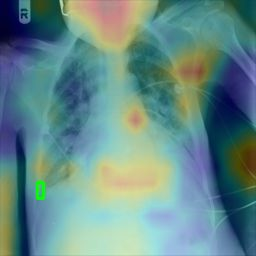

Deployments of artificial intelligence in medical diagnostics mandate not just accuracy and efficacy but also trust, emphasizing the need for explainability in machine decisions. The recent trend in automated medical image diagnostics leans towards the deployment of Transformer-based architectures, credited to their impressive capabilities. Since the self-attention feature of transformers contributes towards identifying crucial regions during the classification process, they enhance the trustability of the methods. However, the complex intricacies of these attention mechanisms may fall short of effectively pinpointing the regions of interest directly influencing AI decisions. Our research endeavors to innovate a unique attention block that underscores the correlation between 'regions' rather than 'pixels'. To address this challenge, we introduce an innovative system grounded in prototype learning, featuring an advanced self-attention mechanism that goes beyond conventional ad-hoc visual explanation techniques by offering comprehensible visual insights. A combined quantitative and qualitative methodological approach was used to demonstrate the effectiveness of the proposed method on the large-scale NIH chest X-ray dataset. Experimental results showed that our proposed method offers a promising direction for explainability, which can lead to the development of more trustable systems, which can facilitate easier and rapid adoption of such technology into routine clinics. The code is available at www.github.com/NUBagcilab/r2r_proto.